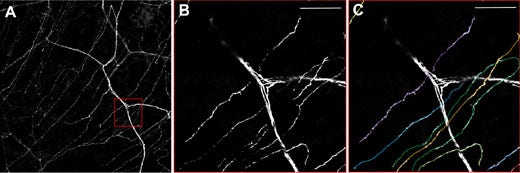

노란색 형광 단백질로 표지된 신경 섬유를 가진 유전자 이식 쥐(thy1-YFP 쥐)를 사용하여 Olympus Fv10i를 통해 체외에서 각막 신경을 시각화합니다. 그림 3은 큰 기질 신경 및 하위기저 신경총의 매우 얇은 신경을 보여줍니다. 하지만 각막의 세포 아키텍처는 복잡합니다.6 그림 4에서 볼 수 있듯이, 이 신경총은 보우만 레이어에 가까이 있고 관통 A 델타신경섬유에서 발생하며 하위기저 방향을 가집니다. Baltrusch 교수는 다음과 같이 언급합니다. “하위기저 신경은 손상에 매우 민감합니다. 당뇨병에 걸린 사람과 동물에서 이러한 신경이 손실됩니다.” 기존 기법과 신규 기법을 비교하고 쥐의 피부 샘플도 분석하면 AGE에 대한 더 많은 수용체가 존재하기 때문에 각막 신경이 훨씬 더 민감한 것을 확인할 수 있습니다.

그림 3: thy1-YFP 쥐의 각막 내 뉴런.

A) 두꺼운 기질 신경 및 하위기저 신경총의 미세한 신경을 보여주는 개관. B)

빨간색 상자 클로즈업 및 C) 단일 하위기저 신경의 정량화. FV10i, 60x 오일 대물렌즈 사용. 기준자 50μm.